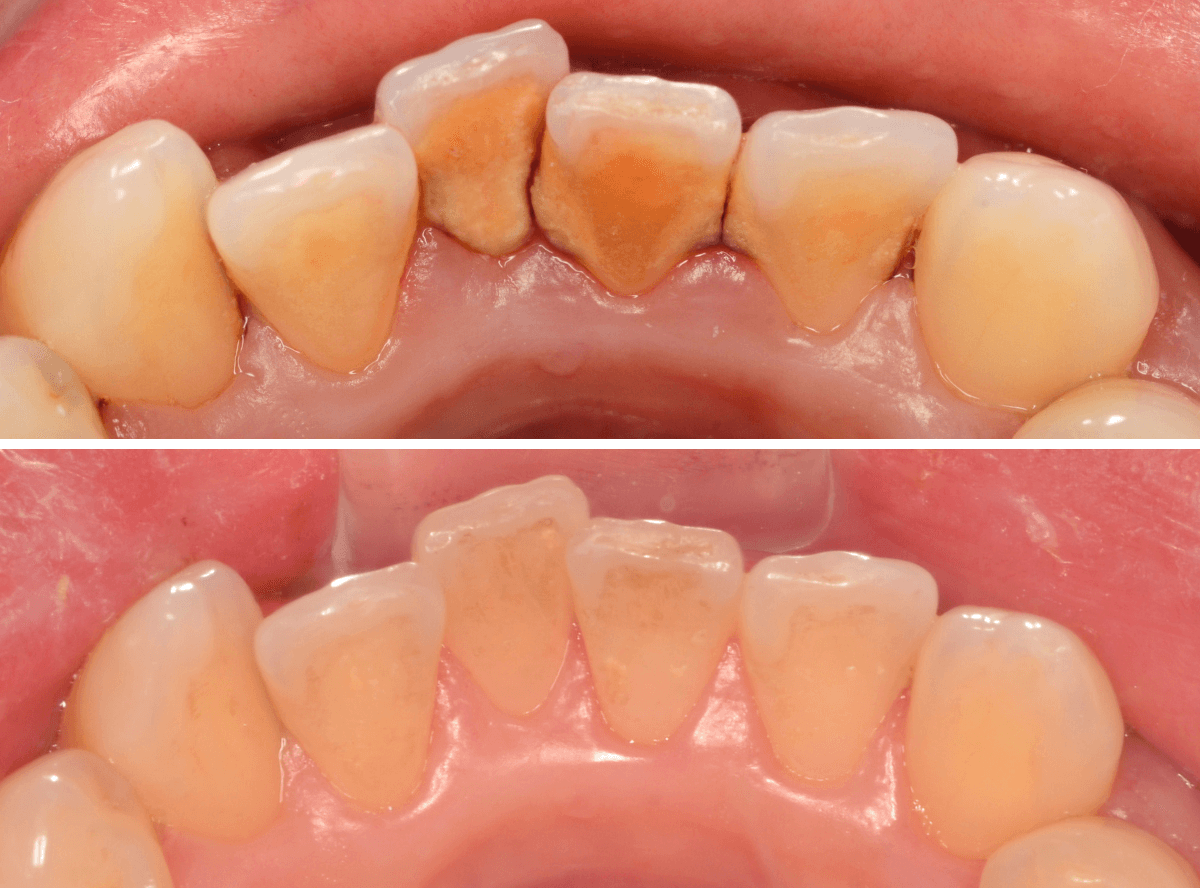

Case.4「歯の周りの黒い物を取って欲しい」という患者さん

今回は、「歯の周りの黒い物を取ってほしい」という訴えの患者さんのケースです。

着色かな、と思い口の中を拝見すると、歯の表面まで露出した縁下歯石でした。

当院は、(現在のところ)比較的若い患者さんが多いので、ここまでハッキリ縁下歯石が露出しているケースは珍しいです。

患者さんには、歯周病の基本的な説明とブラッシング指導をした後、まず下の歯の歯石除去から始めました。

ブラッシング指導・下の前歯の歯石除去直後の写真です。

これだけでも、かなり改善したかと思いますが、これだけの縁下歯石の量ですから、一回の歯石除去で全て取り切れるはずがありません。

根気よく、歯石除去を続ける必要があります。

ビフォー・アフターです。

後日、上の前歯の歯石除去を行いました。

下の前歯の歯肉も改善されてきていますね。

上の歯だけで、これだけの縁下歯石がとれました(まだ歯肉の奥には残っていると思います)。

一度では取り切れません、時間をかけて取っていく必要があります。

かなり歯肉の改善がされていますが、まだしばらく治療は続ける必要があります。